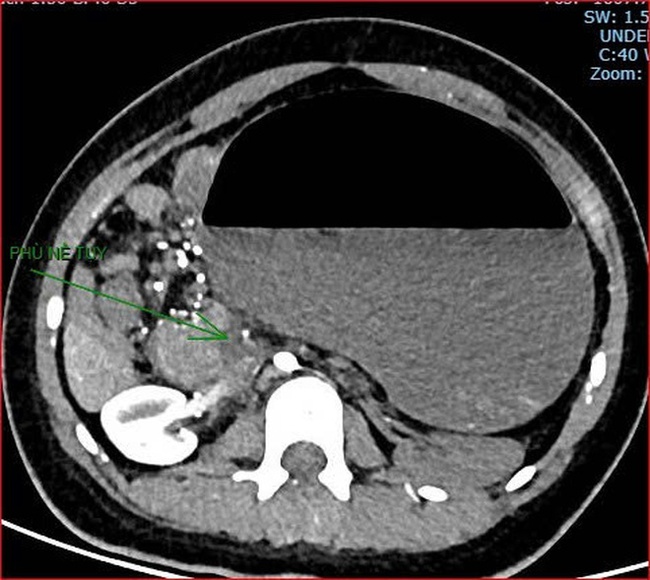

Khoảng 21h40, kết quả chụp CT cho thấy bệnh nhân rơi vào tình trạng cực kỳ nặng và hiếm gặp, bao gồm: Xoắn dạ dày, nhồi máu thận trái, nhồi máu lách, viêm đầu tụy, viêm hỗng tràng, kèm dịch ổ bụng và tràn dịch màng phổi, trên nền bệnh nhân mắc hội chứng Down và tim bẩm sinh.

kết quả chụp CT cho thấy bệnh nhân rơi vào tình trạng cực kỳ nặng và hiếm gặp.